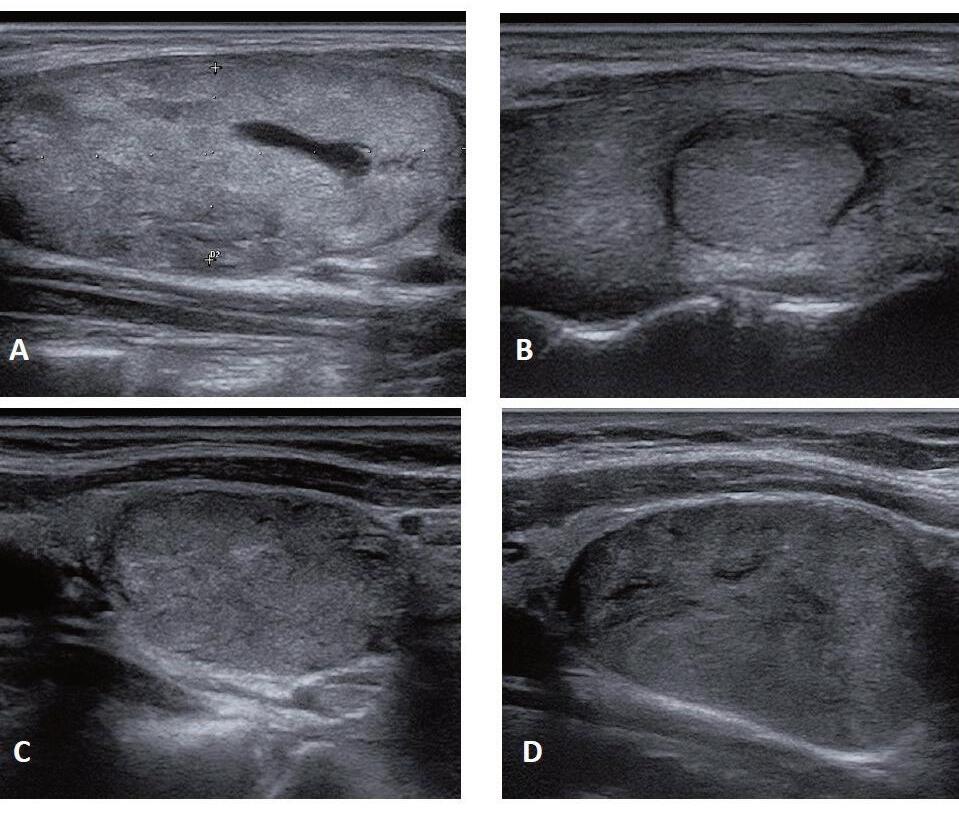

ECOGRAFIA DEL COLLO: STRUMENTO CHIAVE PER LA DIAGNOSI E IL MONITORAGGIO DEL CARCINOMA PAPILLARE DELLA TIROIDE

Giorgio Grani, Antonio Brunetti, Piernicola Garofalo, Giovanni Savoia, Michela Massa, Umberto Crocetti